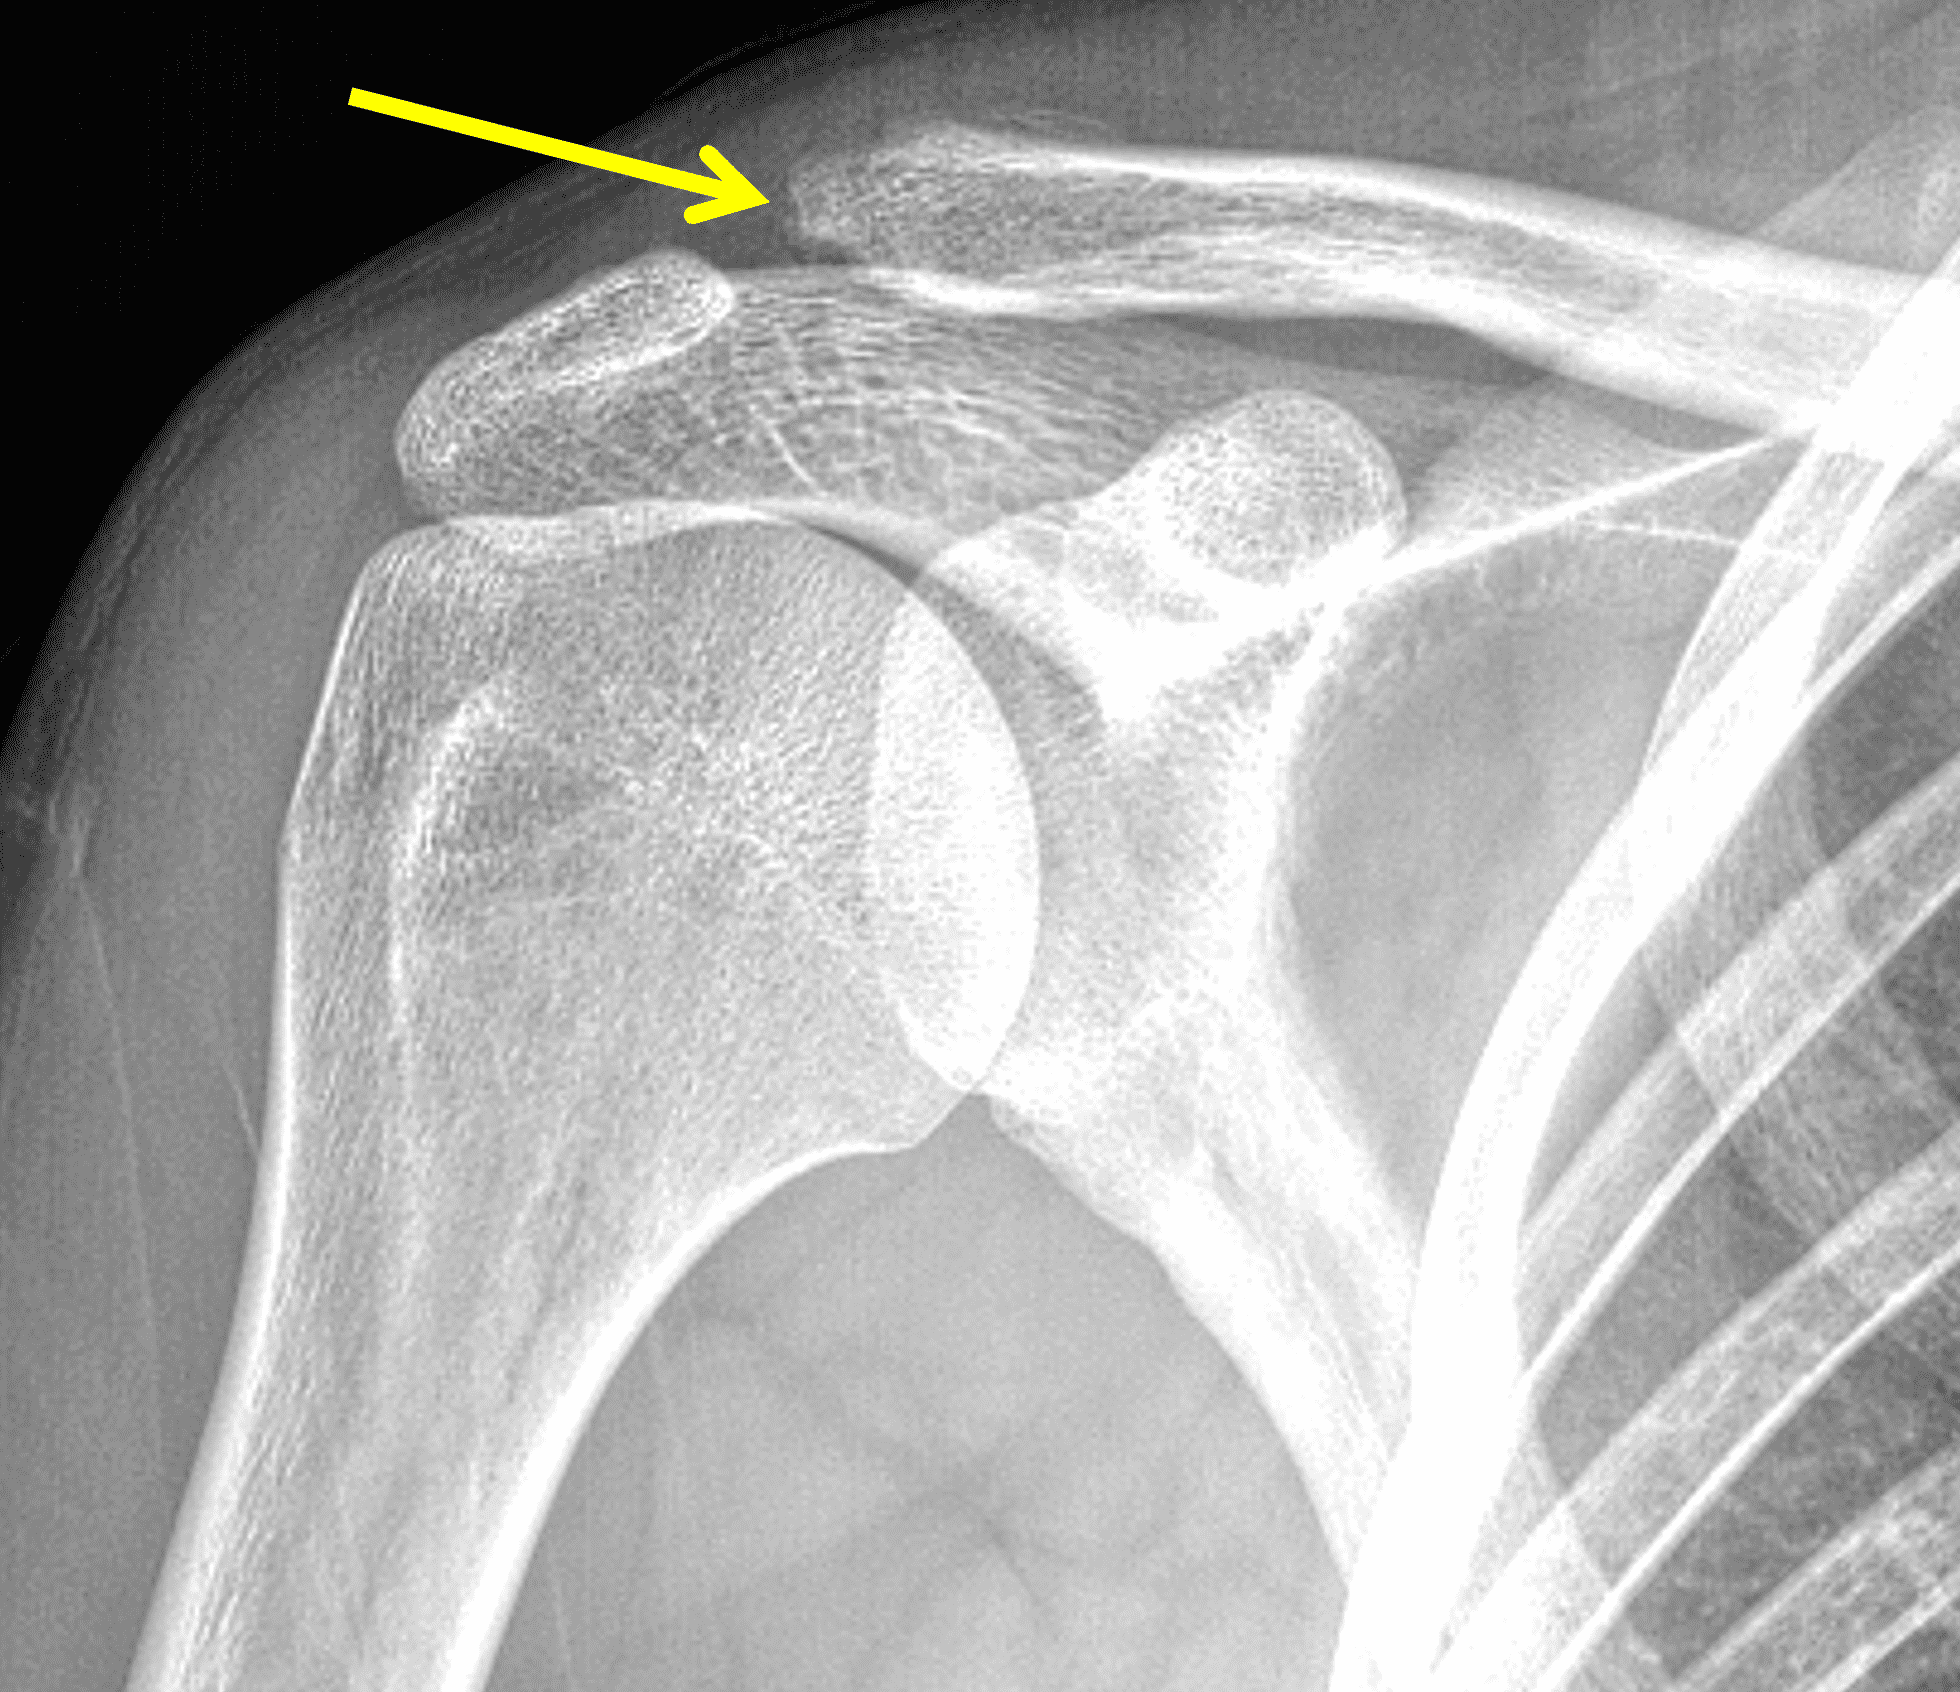

A 49-year-old male, avid weightlifter complains of chronic pain along the superior aspect of his right shoulder. He denies acute trauma. An AP radiograph (Figure 1A), as well as oblique coronal SPAIR (Figure 1B), axial fat-suppressed fluid sensitive (Figure 1C), and oblique sagittal T2-weighted images (Figure 1D) are shown. What are the findings? What is your diagnosis?

Radiographs: Initial radiographs may be normal or show features of other common unrelated AC joint pathology such as osteoarthritis. As inflammation and hyperemia in the distal clavicle progresses, bone density in the distal clavicle can decrease with indistinctness or discontinuity of the subchondral bone plate (Figure 3).  This so-called resorptive phase may also include frank erosions in the distal clavicle or a faint sclerotic line in the medullary space of the distal clavicle parallel to the bone end. Varying degrees of surrounding soft tissue swelling may be visible.  Later, during the late healing phase when symptoms have usually resolved, the distal clavicle may return to a normal radiographic appearance; a sclerotic line parallel to the distal bone end is visible after healing in some cases (Figure 4).  In patients with severe initial bone loss, re-cortication of the resorbed bone and erosions can occur leaving residual bone loss and contour defects in the distal clavicle. While it is typically not a primary modality for the diagnosis of DCO, CT demonstrates the same bone findings as radiographs.